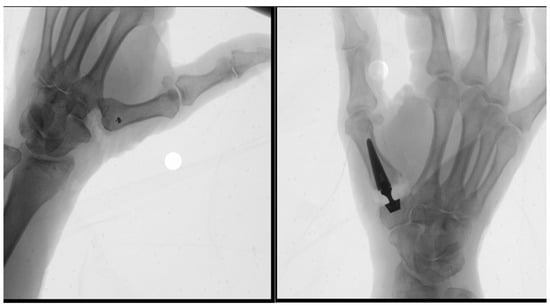

The prosthetic surgery was carried out with the patient in the supine position and a tourniquet applied at the root of the right arm under locoregional anesthesia. The trapeziometacarpal joint was exposed through a lateral surgical approach. The degenerated articular surfaces were resected, and a dual mobility prosthesis (Touch®; Mikai, Italy) was implanted (Figure 2). Capsule closure was performed using absorbable sutures, followed by an intradermal skin suture. A thumb-including bandage was applied for 7 days. After removal of the bandage, a thumb splint was applied, and the patient was encouraged to begin gentle active thumb motion. Fourteen days after surgery, the intradermal sutures were removed, and the patient was allowed to move the thumb freely with a full range of motion.

Figure 2. Intraoperative view showing implantation of the dual mobility prosthesis (Touch®; Mikai, Italy) in the right trapeziometacarpal joint following resection of the degenerated surfaces.

Using the same positioning and locoregional anesthesia, a lateral approach was used for the left hand. The trapezium was excised completely, and a tendon interposition arthroplasty was performed using a slip of the flexor carpi radialis tendon fixed with an anchor on the base of the first metacarpal bone (Figure 3). The joint capsule and soft tissues were sutured to ensure stability and mobility. The wound was closed in layers and dressed, and a cast was applied, with the wrist and thumb included.

Figure 3. Intraoperative view during left hand trapeziectomy with tendon interposition arthroplasty. The trapezium is excised, and a slip of the flexor carpi radialis tendon is fixed with an anchor at the base of the first metacarpal to restore joint function. The wound is closed, and a cast is applied with the wrist and thumb immobilized.

A minimally invasive surgical approach of approximately 2.5 cm, as per our technique, was employed and is demonstrated at the end of the procedure (Figure 4). Immediate postoperative radiographs of both procedures are shown in Figure 5.

Figure 4. Intraoperative view at the end of the procedure demonstrating the minimally invasive surgical approach (approximately 2.5 cm), which characterizes our technique.

Figure 5. Immediate postoperative radiographs following the right trapeziometacarpal prosthetic implantation and left trapeziectomy with tendon interposition arthroplasty. Proper positioning of the dual mobility prosthesis and tendon graft is confirmed.